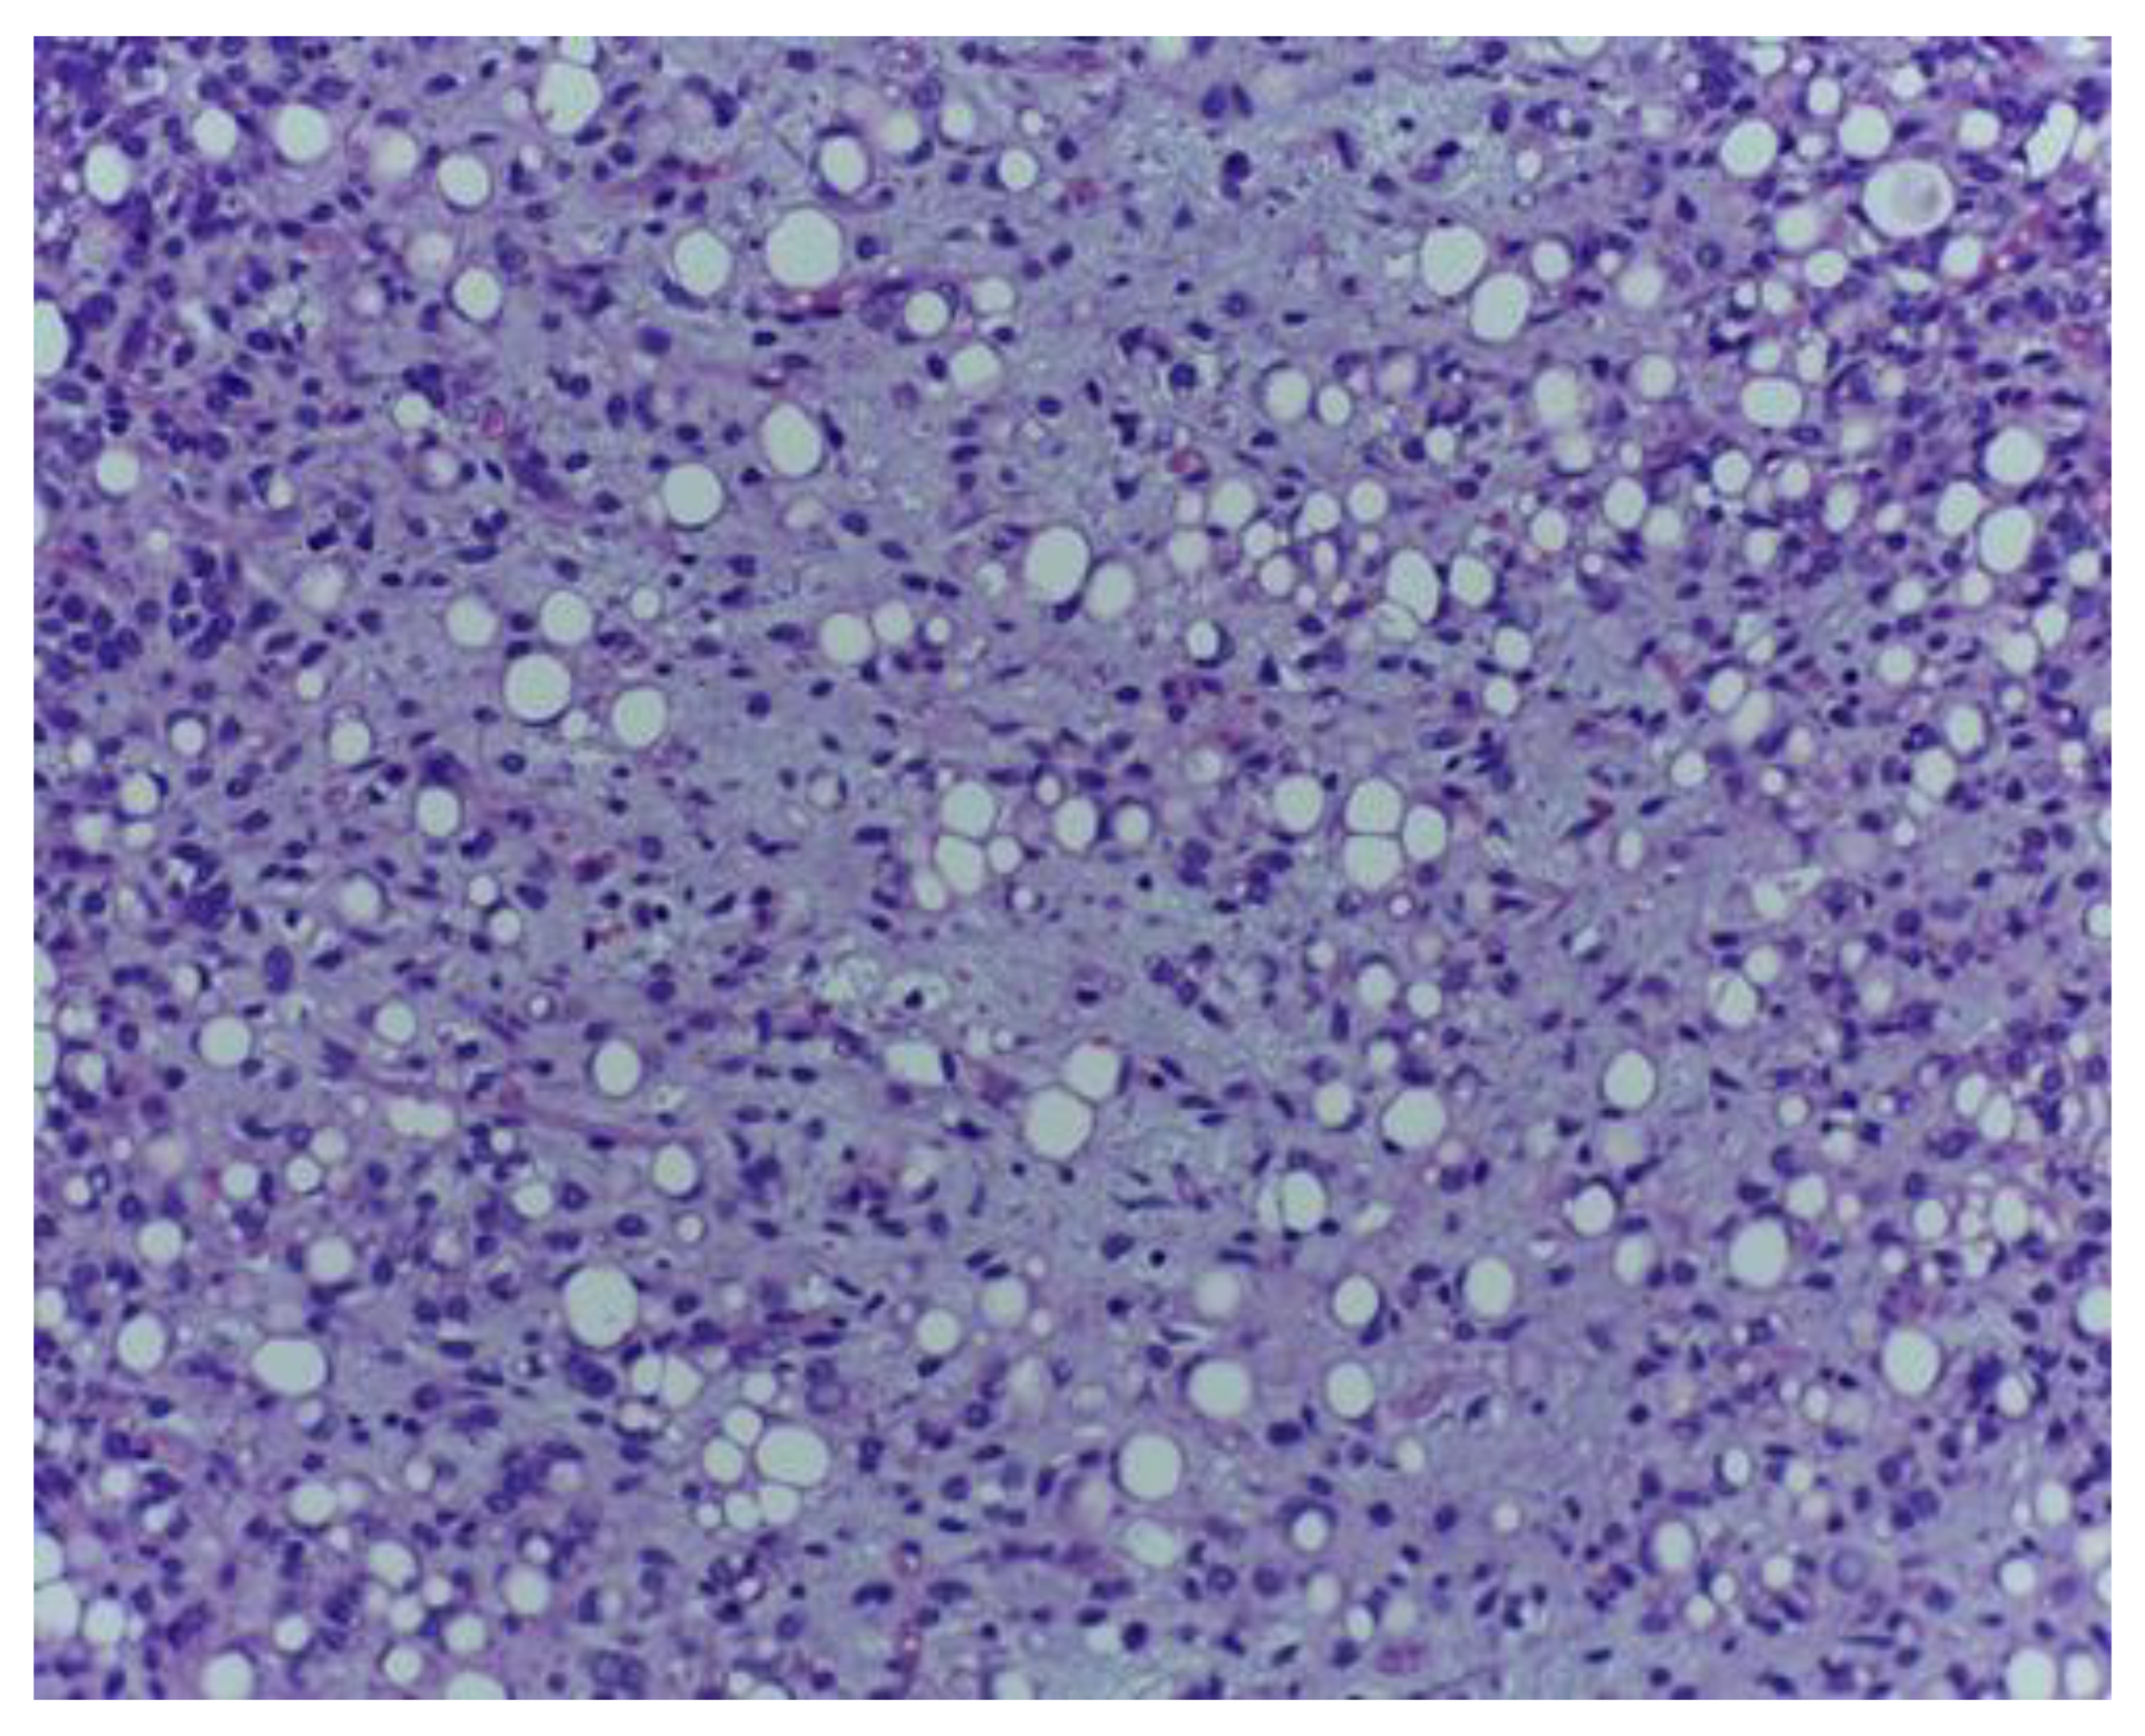

The histological examination showed a malignant mesenchymal proliferation with a lobular growth pattern, exhibiting round–oval and fusiform neoplastic cells with hyperchromatic nuclei and occasional nuclear pseudoinclusions, separated by a loose, lightly basophilic stroma, containing extracellular mucoid pools (Figure 1 and Figure 2).

Figure 1.

Lipogenic tumour component comprising atypical lipoblasts encompassed by a lightly basophilic matrix with myxoid aspect. H.E., ob. 200×.